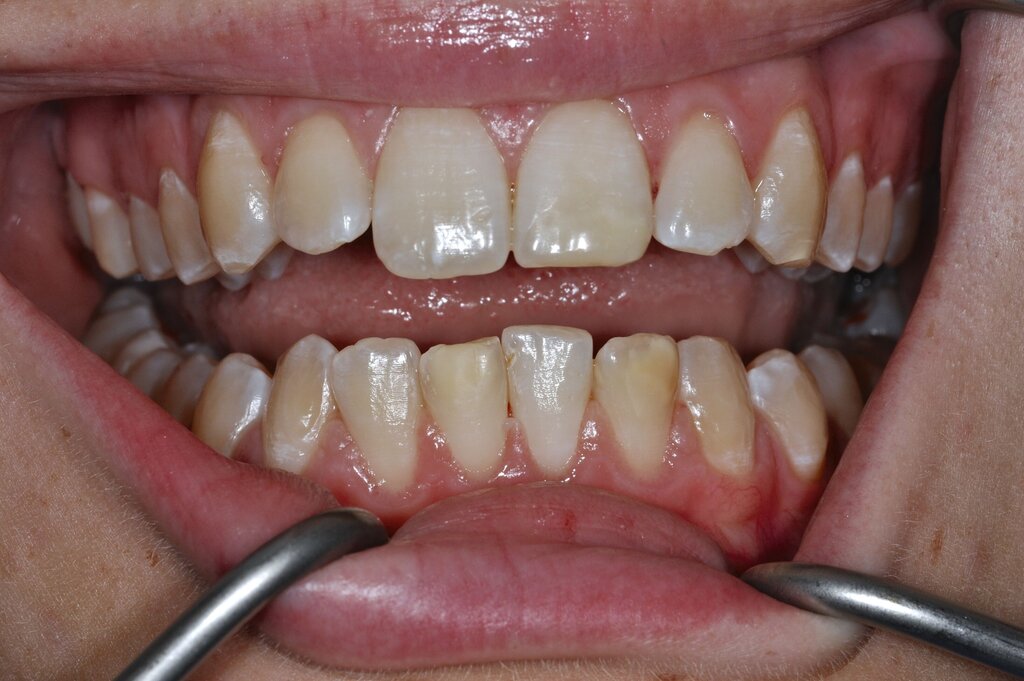

Diese Klassifikation dient als Grundlage für die Therapieempfehlungen. Deutlich wird, dass aufgrund der Symptomatik die Therapie der Zähne höchst unterschiedlich ausfällt. Dass etwa eine Opazität ohne Überempfindlichkeit (Index 1, Abbildung 1) ein anderes therapeutisches Vorgehen erfordert als ein Zahn mit nahezu komplettem Einbruch der Zahnoberfläche und mit Hypersensitivität (Index 4, Abbildung 2), ist offensichtlich.

Für die zahnärztliche Praxis gibt die Einteilung eine Orientierung darüber, welche Behandlungsmaßnahmen erforderlich sind beziehungsweise eingesetzt werden können. Je nach Schweregrad wird dabei zwischen nichtinvasiven und invasiven Maßnahmen sowie einer kurzzeitigen oder längerfristigen, restaurativen Therapie unterschieden. Bei der Überarbeitung des Konzepts wurde zudem zwischen Front- und Seitenzähnen differenziert (Abbildung 3) [Bekes et al., 2023; Steffen et al., 2017].

Die Versorgung der MIH-Frontzähne entspricht dem Vorgehen im Seitenzahnbereich. Problematisch ist die Maskierung der Opazitäten. Dazu müssen opake Komposite verwendet werden und es muss eine Schichtstärke von circa 1,5 mm garantiert sein (Abbildung 9).